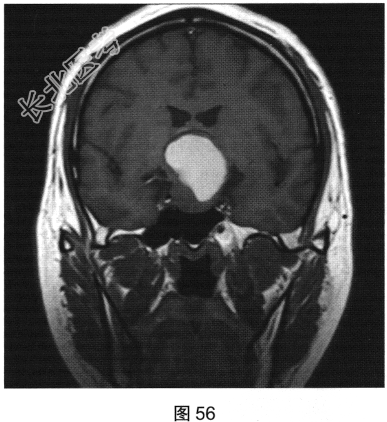

- 多项选择题2.[提示]患者行垂体MRI检查,见图55~图59。患者MRI检查可见哪些阳性影像学表现( )

A、矢状位增强扫描显示垂体及垂体柄显示不清

B、冠状位T1WI上呈等高信号

C、矢状位T1WI上视交叉抬高

D、冠状位T2WI上呈等高信号

E、矢状位T1WI上垂体显示不清

F、冠状位T1WI上可见钙化信号影

G、冠状位增强扫描显示实性部分明显均匀强化

H、MRI示鞍区囊实性占位性病变

I、冠状位增强扫描显示双侧海绵窦受侵